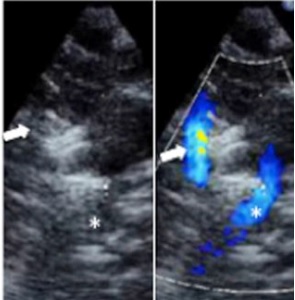

Avant la naissance, le sang d'un fœtus n'a pas besoin d'aller dans les poumons pour s'oxygéner, c'est la circulation sanguine de la mère qui apporte cet oxygène. Ce processus passe par le canal artériel, un lien entre les deux artères principales du cœur qui permet au sang du fœtus de contourner ses poumons. Après la naissance, cependant, le bébé a besoin de respirer par lui-même, de sorte que cette connexion se ferme naturellement ou devrait se fermer naturellement. Cependant, dans certains cas, le canal artériel persiste, ce qui entraîne des difficultés de respiration et d'alimentation, des hémorragies cérébrales et parfois le décès du nourrisson. L'objectif est donc alors de fermer le canal artériel persistant ou de « boucher » ce « trou dans le cœur ». Il existe un traitement médicamenteux, mais il n'est efficace que chez moins de 60% des nouveau-nés concernés et peut causer des effets secondaires tels que l'insuffisance rénale et des saignements. La chirurgie, aussi, comporte ses propres risques et des données récentes suggèrent que les résultats après chirurgie pour les bébés prématurés ne sont pas forcément positifs à long terme. Il existe donc un besoin de traitement plus efficace et moins invasif à la fois. L'équipe du Dr Zahn, expert en interventions cardiaques par cathéter, a donc mis au point une procédure « transcathéter » peu invasive pour la fermeture du canal. Guidé par des ondes ultrasonores, le médecin passe un cathéter par une veine dans la jambe, jusqu'au cœur, et ferme l'orifice. La procédure, de quelques minutes, peut être réalisée en unité de soins intensifs néonatale (USIN).

Un succès dans 70% des cas : La procédure, testée chez 24 enfants extrêmement prématurés nés à 24 à 32 semaines, s'avère un succès dans 21 des cas. 3 bébés dont l'anatomie a empêché la réussite de la fermeture ont subi plus tard une chirurgie réussie.